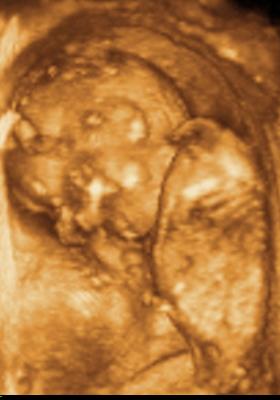

Ui.: Kedden megyünk genetikai UH-ra, szorítsatok nekem. Aztán majd jelentkezem.